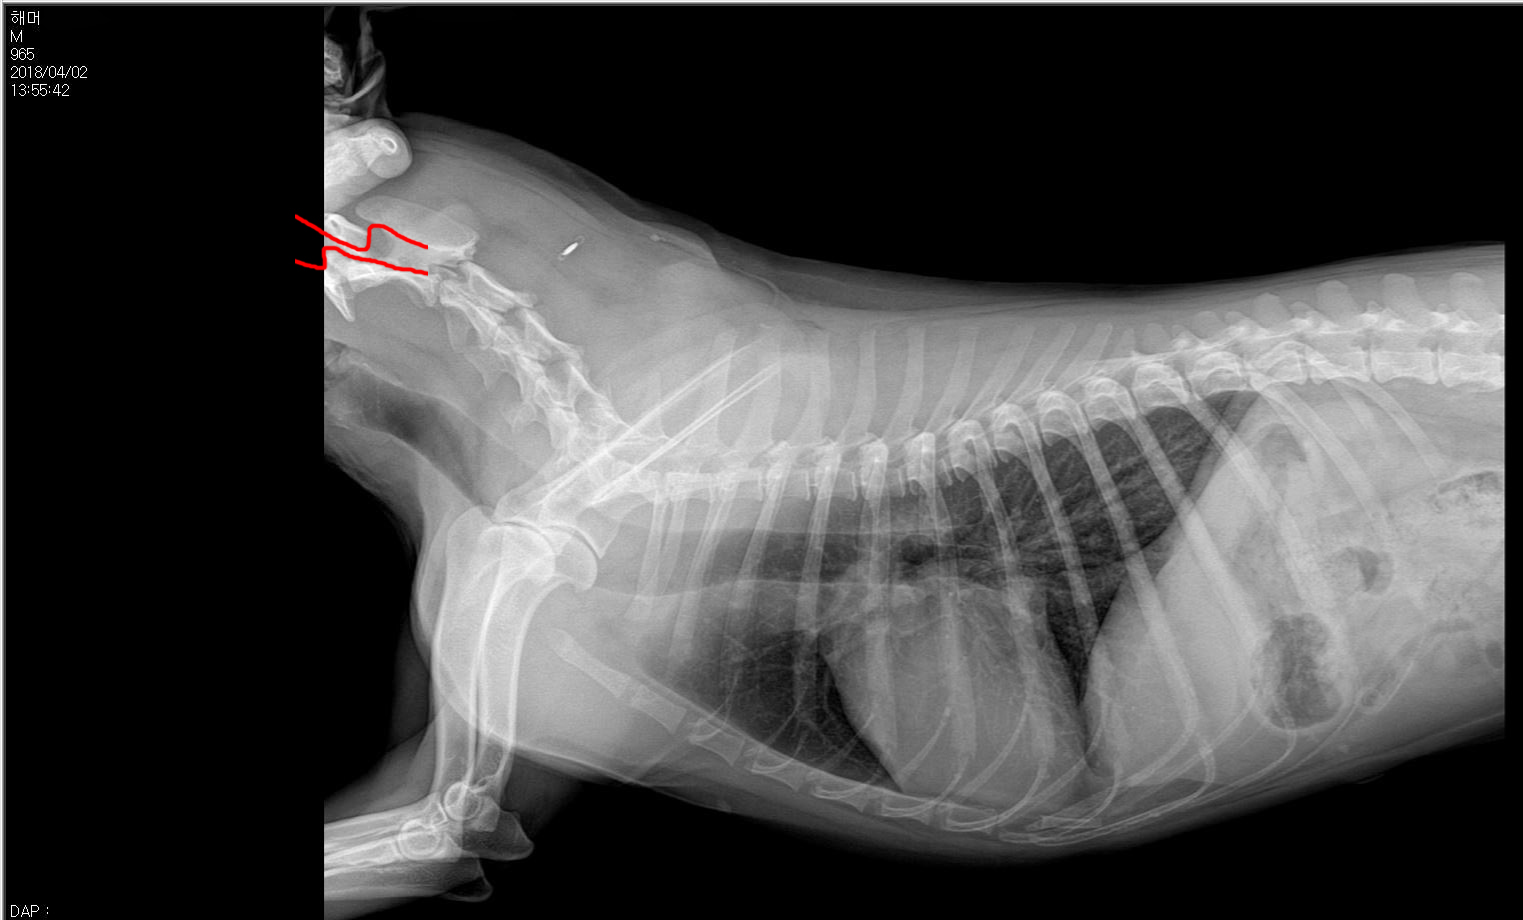

À̹ø¿¡ ÃÔ¿µÇÑ ¹æ»ç¼±»çÁøÀ» ¹ÞÁö´Â ¸øÇß´Ù.

±×·¯³ª À۳⿡ °Ë»çÇÑ ¹æ»ç¼±»çÁø¿¡¼­µµ

¸ñ»À°¡ ÀÌÅ»ÇØ¼­ ô¼ö°¡ Áö³ª°¡´Â Åë·Î¸¦ ´©¸£°í Àִ°Ô

½ÉÁö¾î Áö±Ýº¸´Ù ´õ ºÐ¸íÇÏ°Ô º¸ÀδÙ. £¨µÎ ¹øÂ° »çÁø£©

À̹ø¿¡ Àü½ÅÃÔ¿µÀ» ÅëÇØ¼­ 10³â¸¸¿¡ ¾Ë°ÔµÈ »ç½ÇÀº

ÇØ¸ÓÀÇ ¸Ó¸®»À µÞ ºÎºÐÀº ¸Ó¸®°¡ ±ä Á¾·ùÀÇ °ßÁ¾¿¡¼­

Á¾Á¾ ¹ß°ßµÇ´Â ºñÁ¤»óÀûÀÎ ÇüÅ¿´´Ù.

¼öÀǻ缱»ý´ÔÀº ±× °ÍÀÌ ¼±ÃµÀûÀÎ Àå¾Ö¶ó°í Çϼ̴Ù.

°æÃß°¡ ô¼ö¸¦ ´­·¯¼­, ȤÀº ÈĵκÎÀÇ ¸Ó¸®»À ÀÌÇü¼ºÀÌ

½Å°æÀÇ ¹®Á¦·Î ³ªÅ¸³¯ ¼ö ÀÖ´Ù´Â °ÍÀº

±× Àü³¯ Áø·á½Ç¿¡¼­ µé¾ú´ø ÃÖ¾ÇÀÇ °æ¿ì¿´´Ù.

´Ù½Ã ÃÔ¿µÇÑ ¹æ»ç¼±»çÁø¿¡¼­

°æÃß´Â ¿ÀÈ÷·Á Á¤»ó¹üÀ§·Î µ¹¾Æ°¡ ÀÖ¾ú´Ù.